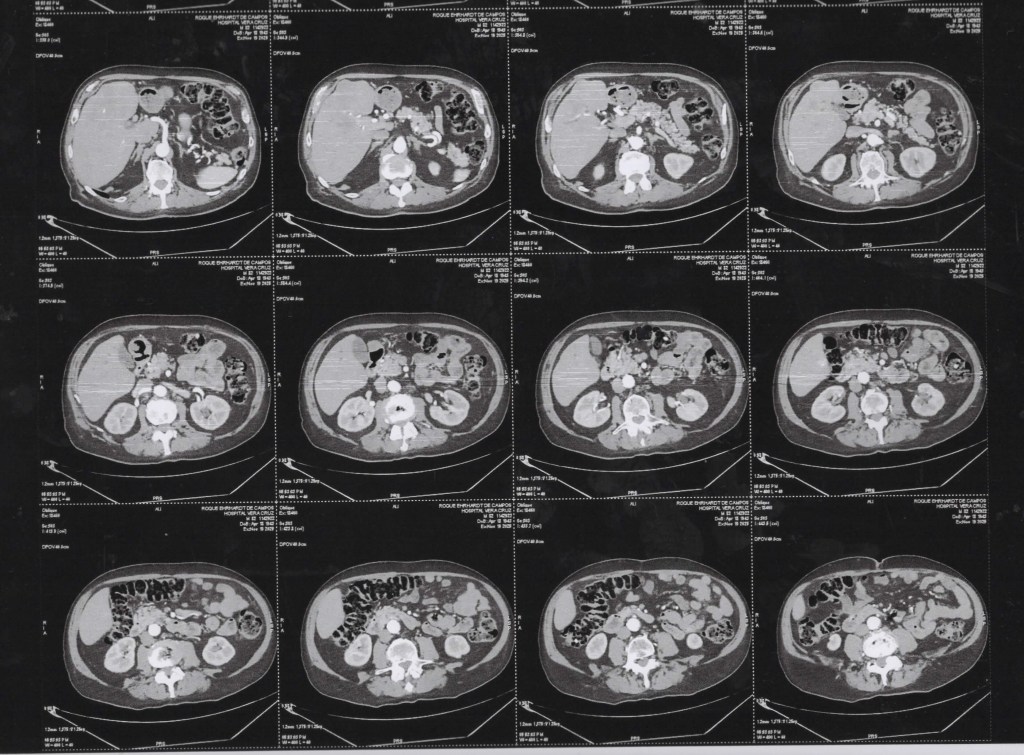

TCM Torax 19 11 2025 Axial janela pulmonar

TCM Torax 19 11 2025 Axial janela pulmonar cortes inferiores

TCM Torax 19 11 2025 janela de mediastino/tecidos moles.

(TC) de Tórax com cortes coronais (vista frontal), em janela pulmonar, com técnica MIP (Maximum Intensity Projection).